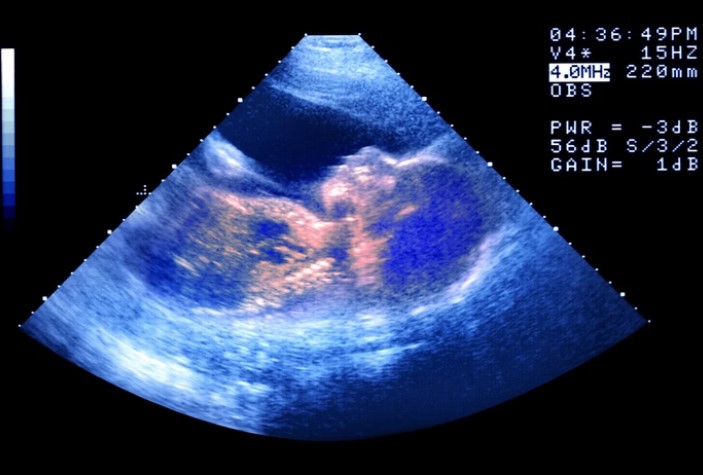

No dia 26 de julho, nasceu em Ohio, nos Estados Unidos, Thaddeus Daniel Pierce, bebê gerado a partir de um embrião congelado em 1994. Com mais de 30 anos entre a fertilização e o nascimento, ele estabeleceu o recorde mundial do embrião humano mais antigo a resultar em parto bem-sucedido.

O embrião foi criado na década de 1990 para Linda Archerd, que teve quatro embriões gerados por fertilização in vitro (FIV). Um deles deu origem a uma menina, hoje com 30 anos, enquanto os outros três foram criopreservados.

O nascimento de Thaddeus destaca uma conquista científica e médica, mas também traz à tona debates éticos, emocionais e sociais sobre a adoção de embriões, preservação da vida embrionária e as escolhas pessoais diante da infertilidade.